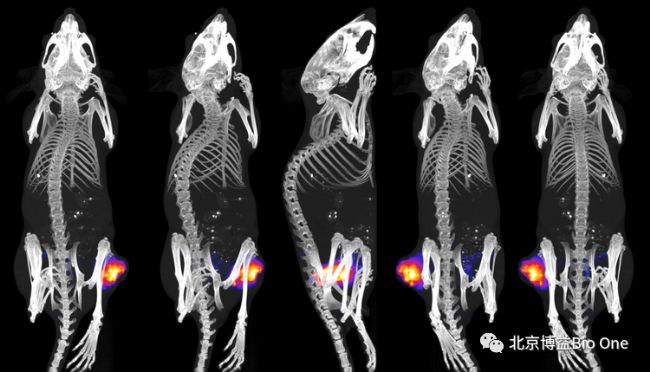

FLECT,全稱(chēng)為熒光發(fā)射計(jì)算機(jī)斷層掃描( FLuorescence Emission Computed Tomography),是一種光學(xué)分子成像方法,它利用完整角度的斷層掃描,進(jìn)行數(shù)據(jù)采集,類(lèi)似于現(xiàn)有的PET、SPECT等斷層成像模式,但FLECT無(wú)放射性同位素,屬于光學(xué)模擬的PET和SPECT。FLECT的獨(dú)特之處在于,光學(xué)系統(tǒng)安裝在一個(gè)圍繞動(dòng)物旋轉(zhuǎn)的機(jī)架上,在活體狀態(tài)下對(duì)熒光發(fā)射信號(hào)進(jìn)行360°采集,獲取完整角度的斷層圖像數(shù)據(jù)。在準(zhǔn)確性和靈敏度方面優(yōu)于其他具有有限角度光學(xué)成像功能的儀器所使用的光柵掃描方法。FLECT采用近紅外(NIR)熒光的檢測(cè)手段,適用于小鼠體內(nèi)深部組織的成像。

3、工作原理InSyTe FLECT / CT是一個(gè)小動(dòng)物活體成像平臺(tái),將FLECT熒光成像與同軸一體化的X射線CT掃描整合到一個(gè)儀器中,提供具有解剖學(xué)參考的光學(xué)分子成像功能。FLECT熒光成像單元標(biāo)準(zhǔn)配置有4個(gè)NIR激光器(642 nm,705 nm,730 nm,780 nm)和相應(yīng)的NIR熒光發(fā)射濾光片。成像時(shí),激光直接導(dǎo)入FLECT準(zhǔn)直器組件中,激發(fā)小鼠體內(nèi)的熒光。一個(gè)由48個(gè)光電二極管組成的探測(cè)器環(huán)環(huán)繞在小鼠周?chē)占l(fā)出的熒光信號(hào)。

InSyTe FLECT / CT是一種雙模態(tài)的臨床前分子成像平臺(tái),可將完整角度的熒光斷層成像與X射線CT掃描結(jié)合于一體。

使用InSyTe FLECT / CT獲取光學(xué)圖像,熒光數(shù)據(jù)可以采用2D或3D(完整角度)兩種方式進(jìn)行采集。

同軸一體化X射線CT掃描模塊的配備,使InSyTe FLECT / CT可以執(zhí)行具有解剖學(xué)參考的無(wú)創(chuàng)、無(wú)放射性同位素的3D斷層成像,并可以輕松地安裝在標(biāo)準(zhǔn)實(shí)驗(yàn)室或臨床前成像設(shè)施中。